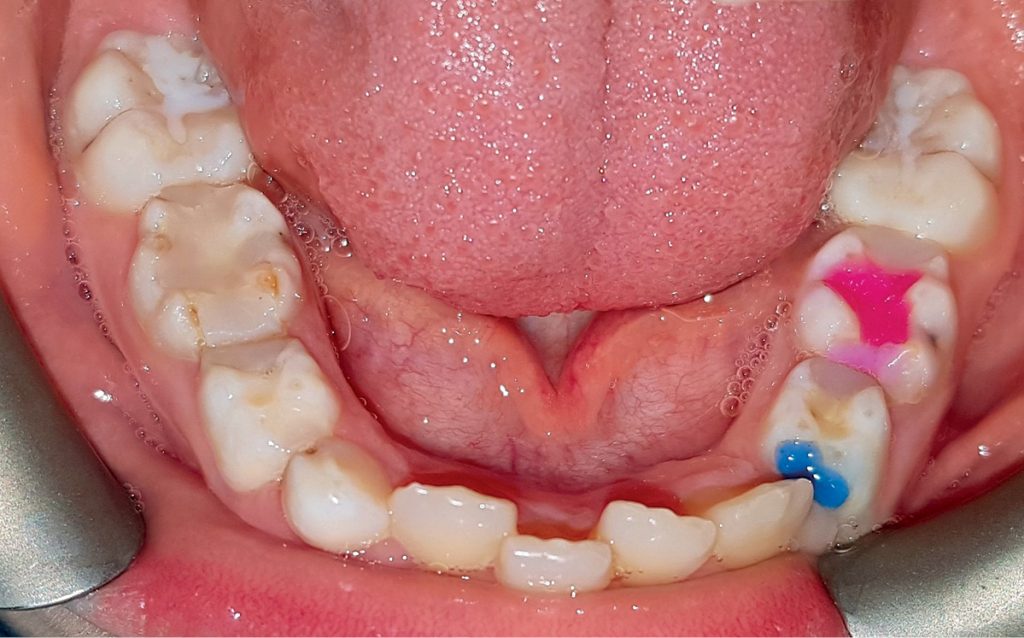

Streszczenie: Występowanie i rozwój próchnicy zależą od wielu czynników. Związek między chorobą próchnicową a wadami ortodontycznymi u dzieci nie jest dobrze poznany. Wyniki badania własnego pokazują, że u dzieci leczonych ortodontycznie próchnica występuje nieznacznie rzadziej niż u dzieci z prawidłowym zgryzem, ale za to charakteryzuje się większą intensywnością. Ponadto zaobserwowano, że u małoletnich pacjentów aparaty stałe mają bardziej niekorzystny wpływ na higienę jamy ustnej i stan uzębienia niż aparaty wyjmowane.

Summary: The occurrence and development of dental caries depend on many factors. The association between dental caries and malocclusion in children is not well known. Based on our research results, it can be concluded that caries in children undergoing orthodontic treatment is slightly less frequent than in children without malocclusion, but it is more intense. In addition, more destructive effect of fixed appliances than of removable appliances on oral hygiene and dental status in adolescent patients was [...]